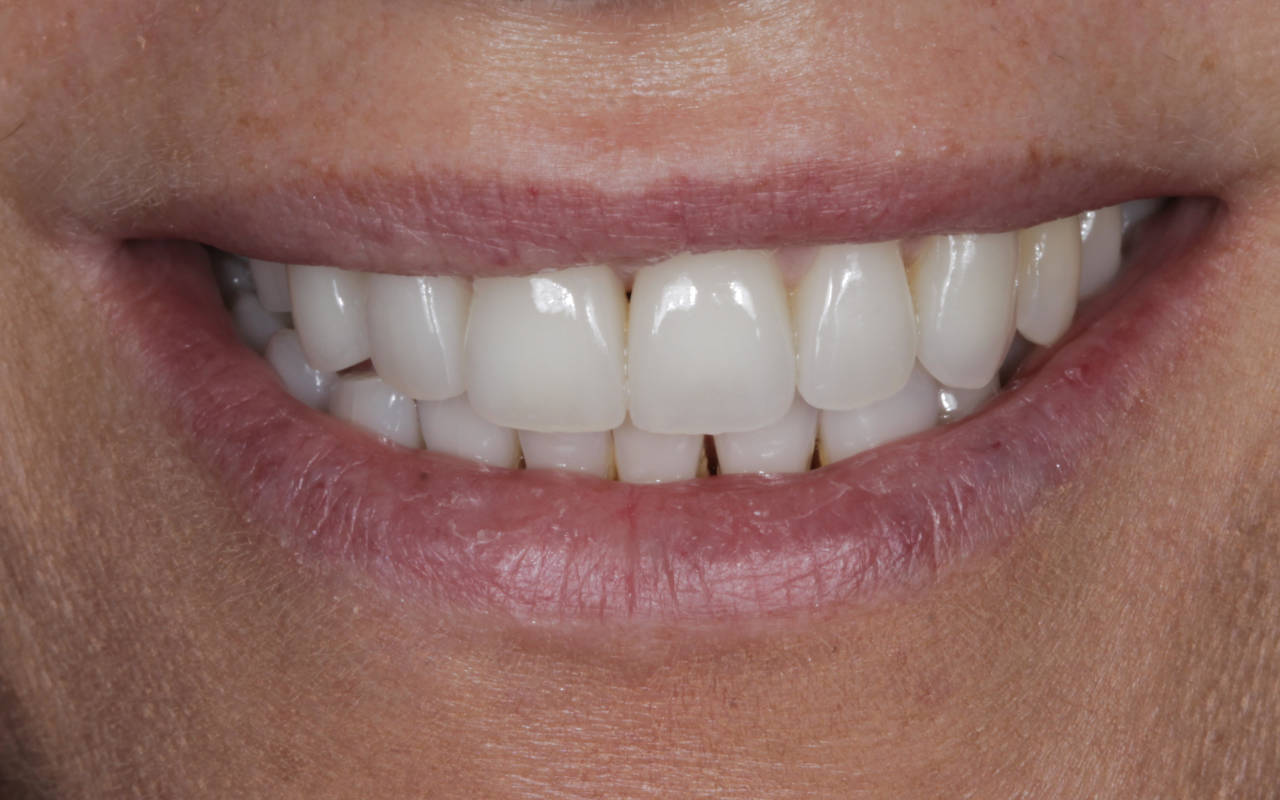

A harmonização do sorriso fez toda a diferença nes